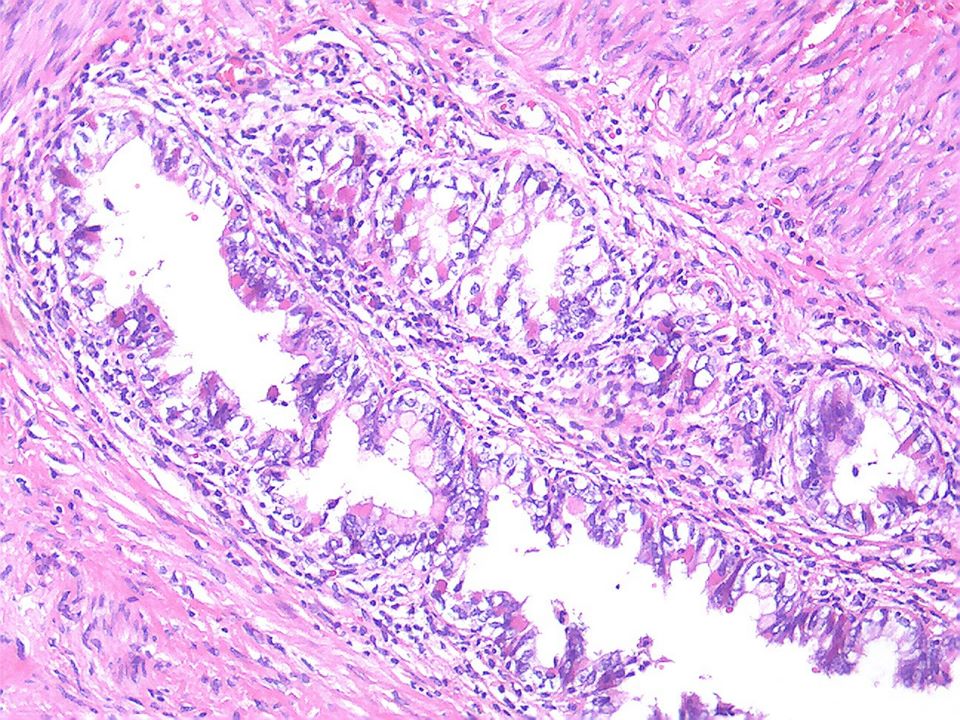

Про гистологию

Про гистологию 84 фотографий